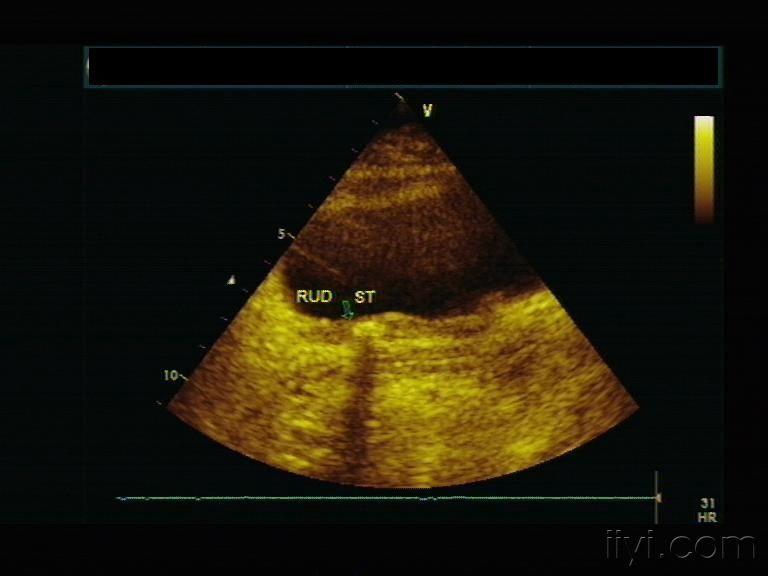

输尿管超声手法图解,输尿管扩张超声图片

输尿管扩张超声图片

超声图像